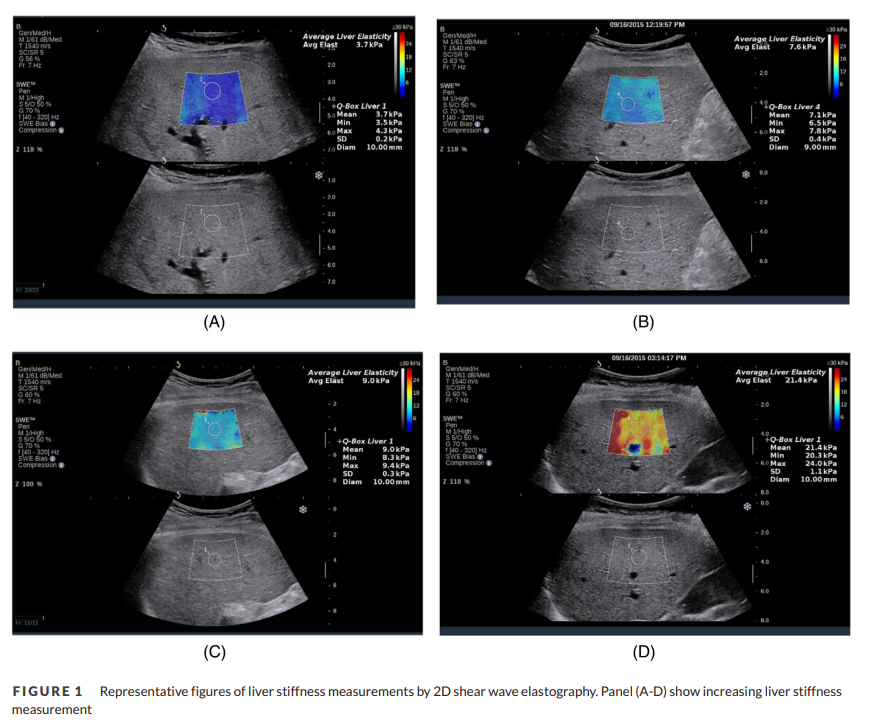

Liver elastography is a good biomarker of venous congestion and is associated with 🫀failure outcomes: study from Nishah Panchani MD and Sumeet Asrani When will we see trials of change in liver elastography as target for CHF hospitalization? Or have we? pubmed.ncbi.nlm.nih.gov/34817905/

Liver elastography is a good biomarker of venous congestion and is associated with 🫀failure outcomes: study from <a href="/NishahPanchani/">Nishah Panchani MD</a> and <a href="/AsraniSumeet/">Sumeet Asrani</a>

When will we see trials of change in liver elastography as target for CHF hospitalization? Or have we?

pubmed.ncbi.nlm.nih.gov/34817905/